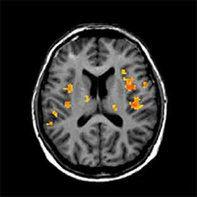

Diffusion-Perfusion

Besondere Untersuchungssequenzen existieren für die Darstellung von Entzündungen, Blutungen oder Tumoren, zur Epilepsiediagnostik oder zur Abklärung von Durchblutungsstörungen. Frühzeitig können Schlaganfälle beurteilt werden und ursächliche Verengungen der Blutgefäße gleich mit dargestellt werden (MR-Angiographie).

Funktionale MRT

Die MRT erlaubt die Darstellung von Stoffwechselveränderungen (MR-Spektroskopie) und spezieller Hirnfunktionen (funktionelle MRT). Neben dem Einsatz in der Hirnforschung lassen sich mithilfe dieser Methoden auch Hirnoperationen besser planen.